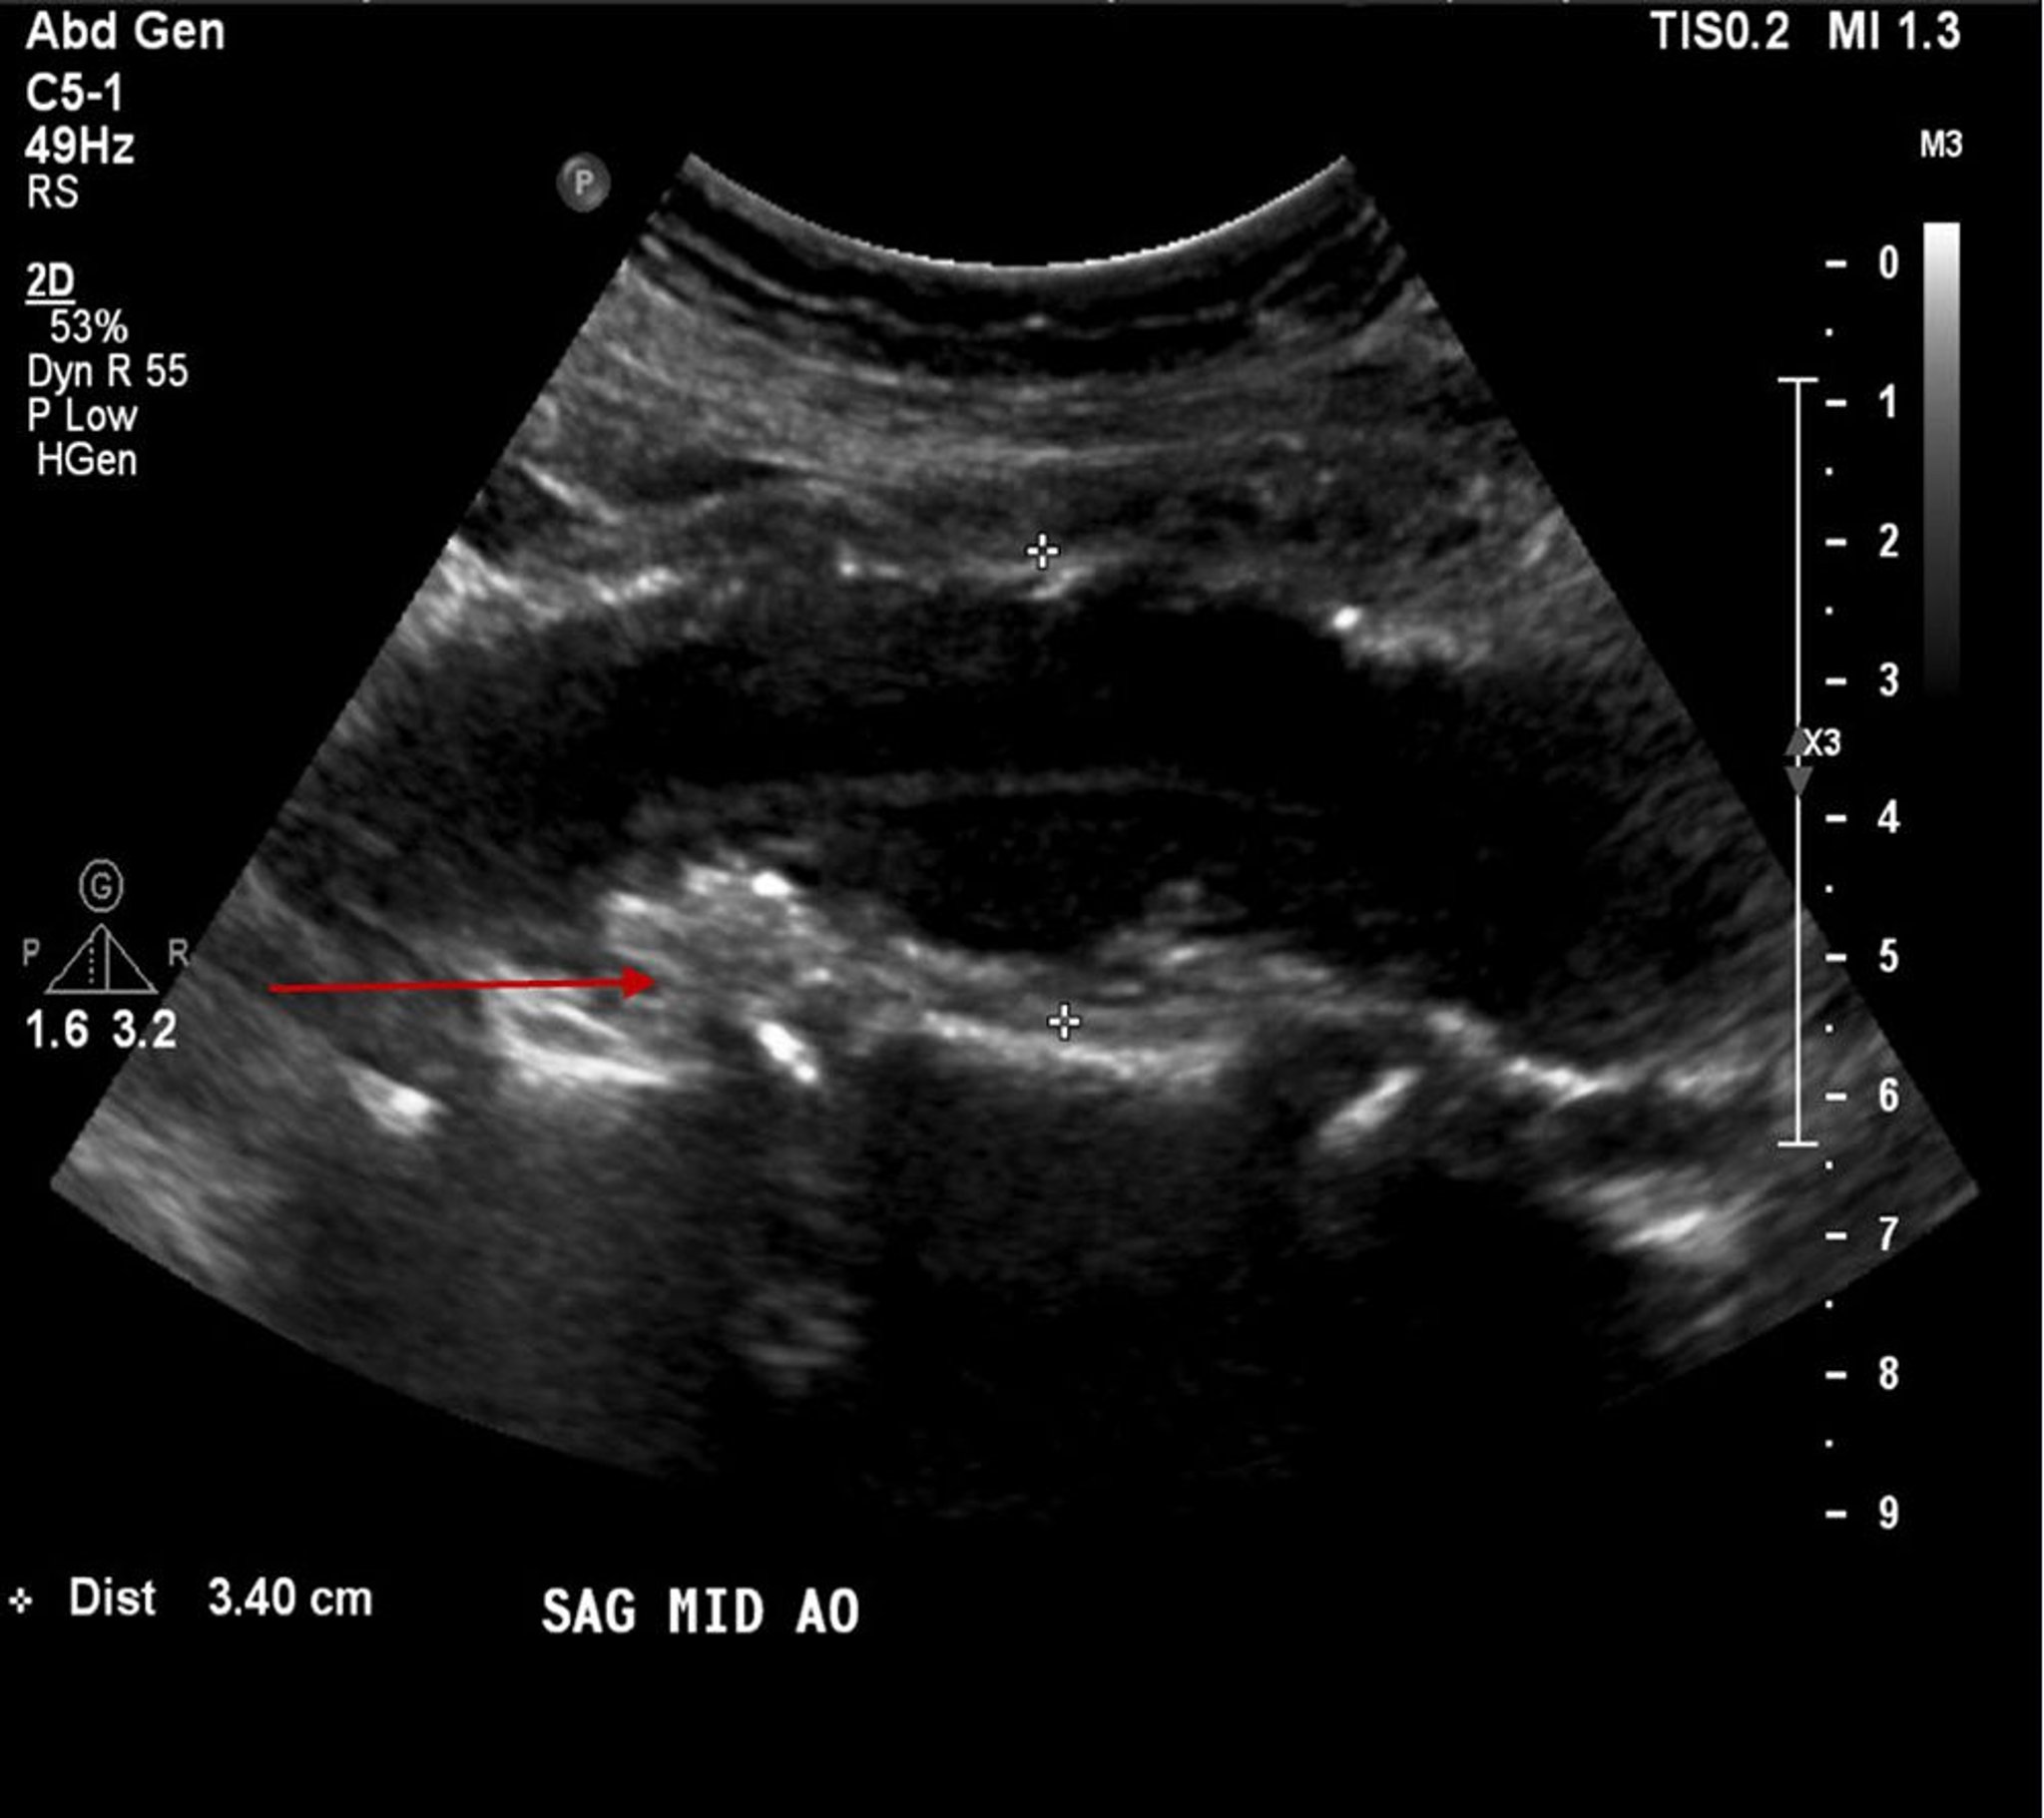

Anévrisme de l'aorte abdominale (échographie)

Ce patient a un anévrisme de l'aorte abdominale mesurant 3,4 cm ainsi (entre les croix blanches) qu'une plaque athéroscléreuse ou un thrombus mural (flèche rouge).

© 2017 Elliot K. Fishman, MD.